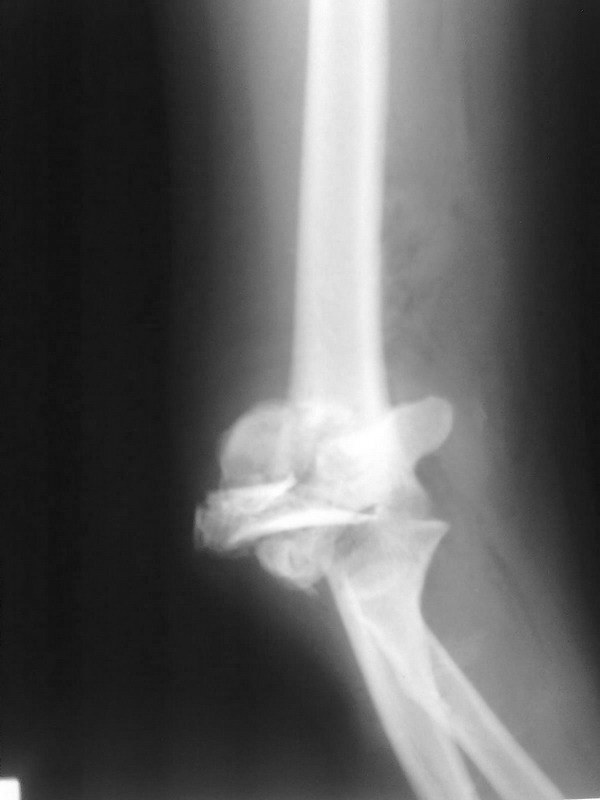

Вялоконсолидирующися чрезмыщелковый перелом плеча

Уважаемые коллеги. Помогите советом определится с тактикой дальнейшего лечения. Пациентка, 16 лет. В 02.2011 - тяжелая сочетанная травма ОДА, груди, живота. В т.ч.открытый многооскольчатый чрезмыщелковй перелом правого плеча и локтевого отростка

Прооперирована на 2 сутки - остеосинтез реконструктивными пластинами плеча и локтевого отростка по типу Weber. В мае 2011 - явления спицевого остеомиелита на фоне слабой консолидации . Спицы удалены. Свищи закрылись. Больная ушла на реабилитацию в поликлинику.

На томографе от 09.2011 - вялая консолидация перелома плеча и локтевого отростка. на томографе от 02.2012 - картина схожая - вялоконсолидирующийся перелом правого плеча, вялоконсолидированный перелом локтевого отростка, угловая деформация по типу варусной. Контрактура локтевого сустава - сгибание 100, разгибание 80, супинация 45, пронация 40.

В наших планах выполнить костную пластику с удалением реконструктивных пластин и с установкой LCP пластин, есть ли смысл в остеотомии для коррекции варуса?. И будет ли смысл в этом. Хотелось бы увеличить амплитуду движений в суставе. Реально ли это на фоне такой картины?. Заранее спасибо